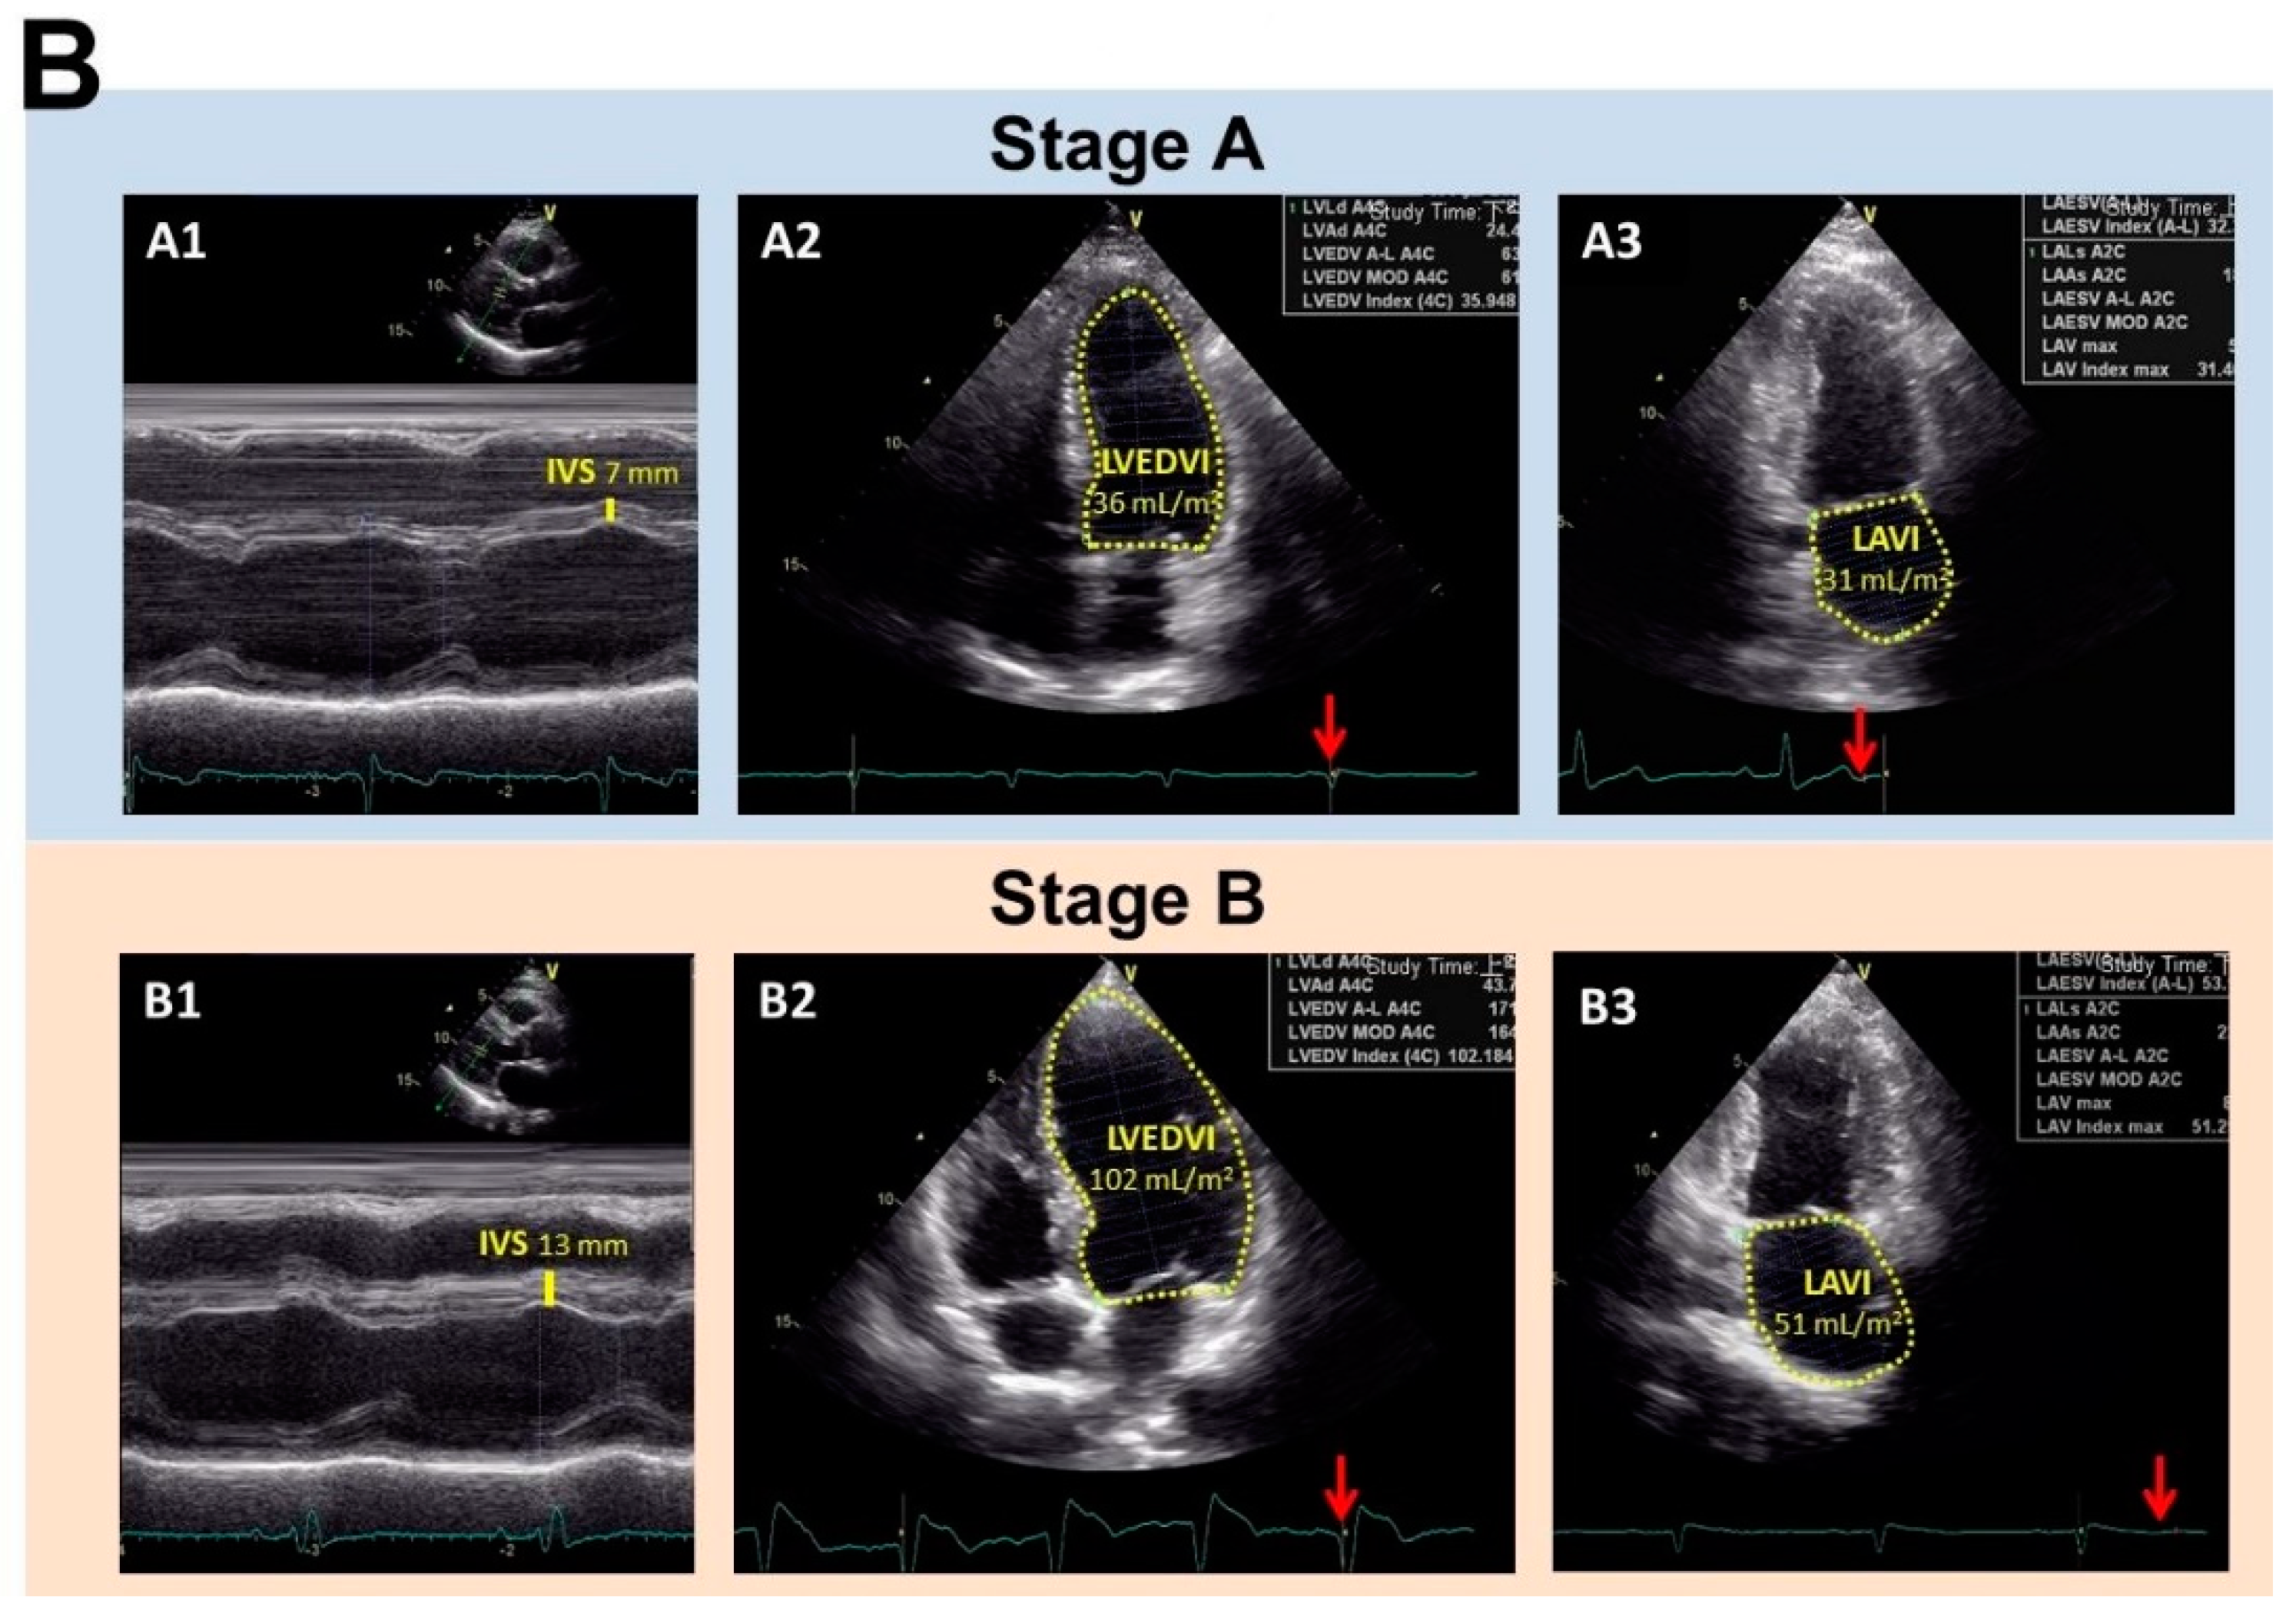

Representative echocardiographic images and the NT-proBNP levels of subjects in Stage A and B heart failure (HF). (A) The NT-proBNP levels of the subjects in Stage A and B HF. * indicated p < 0.05 by independent t-test. (B) Upper panel: a 68-year-old male subject with Stage A HF (body surface area (BSA) of 1.8 m2). His echocardiographic parameters, including interventricular septum thickness (IVS; A1, 7 mm, normal range 6–10 mm), left ventricle end diastolic volume index (LVEDVI; A2, 36 mL/m2; normal range < 95 mL/m2), and left atrium volume index (LAVI; A3, 31 ml/m2; normal range < 34 mL/m2) were within normal ranges. Bottom panel: a 70-year-old male subject with asymptomatic Stage B HF (BSA 1.9 m2). The echocardiographic examination results demonstrated myocardial remodeling, including thickened IVS (B1, 13 mm) and enlarged LVEDI (B2, 102 mL/m2) and LAVI (B3, 51 mL/m2). The red arrow indicates that the echocardiographic pictures were taken at the end-diastolic phase in A2 and B2, and at the end-systolic phase in A3 and B3.

A total of 162 subjects were recruited into the study between February 2019 and November 2019. The demographic and clinical baseline characteristics of the subjects are shown in Table 1. Of these, 113 subjects (70%) had Stage A HF and 49 subjects (30%) had Stage B (asymptomatic) HF. Both groups had a male predominance and the ASCVD risk scores in both groups were in the high category (>20%). The risk factors for HF included coronary artery disease as well as hypertension and diabetes, and these were similar for both groups. Biochemical analysis showed that the Stage B HF group had higher levels of NT-proBNP (Figure 1A, 117.35 ± 114.93 vs. 78.30 ± 87.55, p = 0.040) and adiponectin (13.13 ± 10.32 vs. 8.74 ± 8.86, p = 0.011). Our results demonstrated that elevated serum levels of NT-proBNP and adiponectin correlated with the progression of HF in asymptomatic patients. Despite the beneficial effects of adiponectin on cardiometabolic traits, increased adiponectin has also been found during HF progression, the so-called adiponectin paradox [15]. Echocardiography analysis showed that both groups had adequate LV systolic function and right ventricle systolic function, as shown by the LVEF, global longitudinal strain analysis, and tricuspid annular plane systolic excursion parameters. Since Stage B HF is defined as having LV hypertrophy, dilatation, increased relative wall thickness, and/or LVdysfunction, the corresponding echocardiographic parameters were greater in the Stage B group as would be expected (Table 2; Figure 1B). Following multiple logistic regression analyses, it was found that an elevated NT-proBNP level was associated with a prediction of Stage B HF (odds ratio: 1.005, 95% confidence interval 1.000–1.010, p = 0.032; Table 3).